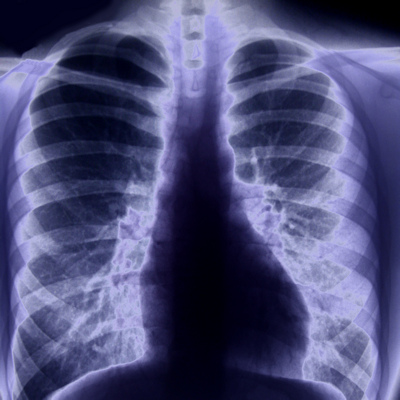

The role of chest CT and x-ray in the management of COVID-19 has not been fully explored, Rubin and colleagues noted. The Fleischner Society statement presents the perspectives of 15 thoracic radiologists, 10 pulmonologists, one pathologist, and experts from emergency medicine, infection control, and laboratory medicine. The panel included clinicians from the U.S., Italy, China, Germany, France, the U.K., the Netherlands, South Korea, Canada, and Japan -- nine of the 15 countries with the highest number of COVID-19 cases reported worldwide as of April 1.

- Imaging is not routinely indicated in asymptomatic patients or those with suspected COVID-19 and mild symptoms unless they are at risk of disease progression.

- Chest imaging is indicated in patients with COVID-19 with declining respiratory status, as well as those with moderate to severe features of COVID-19 regardless of test results.

- In environments where supplies such as personal protective equipment or COVID-19 tests are scarce, imaging is recommended to triage patients with moderate or severe clinical features of the disease.

- CT is indicated in patients with functional impairment or low levels of oxygen in the blood after recovery from COVID-19.

- When COVID-19 is identified incidentally on chest CT, patients should have reverse transcription polymerase chain reaction (RT-PCR) testing.